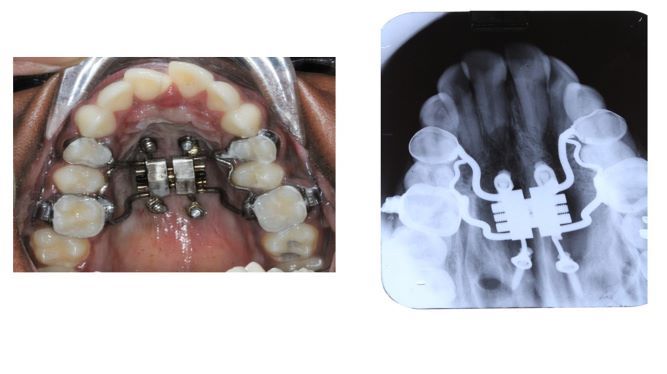

CASE 4: 19yr old female came with complaint of mal-aligned tooth. On examination and investigation maxillary arch constriction with posterior bilateral crossbite observed. MARPE appliance is inserted to correct maxillary constriction.